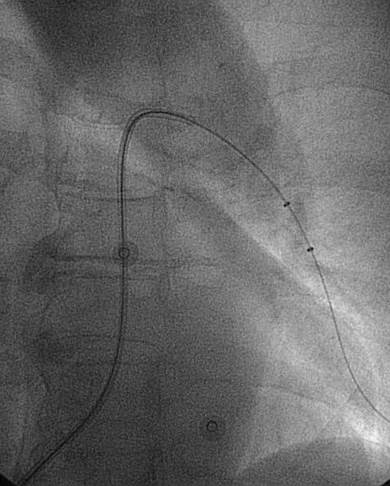

Angiografía de la arteria pulmonar derecha realizada con un catéter en espiral de 6 F en ángulo, que demuestra la presencia de un trombo de gran tamaño dentro de la arteria pulmonar derecha y en las bifurcaciones lobulares intermedia, inferior y superior.

Se efectuó una trombectomía reolítica con el catéter PE de AngioJet® mediante un catéter guía multifunción de 8 F y una guía de angioplastia hidrófila de 0,035’’, en las bifurcaciones lobulares intermedia e inferior.

Angiografía pulmonar derecha realizada tras una trombectomía reolítica en la que se muestra la mejora de los índices de perfusión y obstrucción.